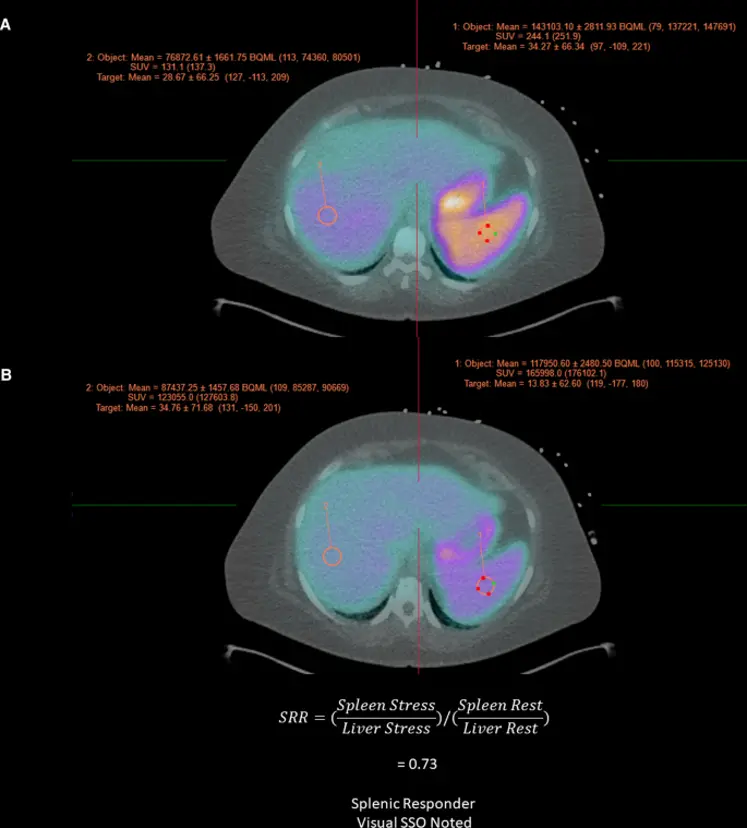

Fusiontab → pull up the Stress and Rest images - Splenic shut-off (SSO; aka splenic switch-off) is a marker of adequate vasodilator response to pharmacologic stress. Recall, failure to induce proper coronary hyperemia may result in false-negative studies.

- SSO describes a decrease in splenic radiotracer activity from rest to stress. Lack of SSO based on visual or quantitative assessment can help identify inadequate vasodilatory response.

Figure source: https://pubmed.ncbi.nlm.nih.gov/36607537/

Example of Splenic Shutoff without Perfusion Defects

57-year-old male with hypertension, diabetes mellitus, and chronic kidney disease who presented for the evaluation for suspected CAD. A PET-MPI imaging revealed normal relative regional with no identifiable perfusion defects. (B) However, albeit a normal resting myocardial blood flows, the patient’s stress myocardial blood flow remained unchanged following the administration of regadenoson with a severely reduced myocardial flow reserve of 1.09. Assessing the patient’s hemodynamic responses, we can also note an unchanged heart rate (75 bpm rest vs 76 bpm stress) and failure to observe expected EF enhancement (36% at rest vs 37% at stress). The patient’s coronary artery calcium score (6246) only served to increase the concern for CAD. (C) Inspection of the spleen (white arrows) reveals a failure to exhibit visual signs of splenic switch-off (SRR was 1.1). Based on these findings, the patient was recommended to obtain an invasive catheterization due to growing suspicion of non-response to regadenoson. D ICA revealed a significant obstructive coronary artery disease LAD (Left Anterior Descending) lesion (yellow arrow) 1